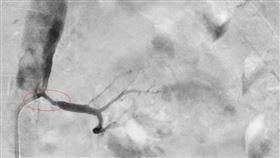

下猛藥仍無法降血壓是這問題 差點爆血管

65歲許先生有三高慢性病及心血管狹窄的冠心症病史,近...

2022/11/10 18:25